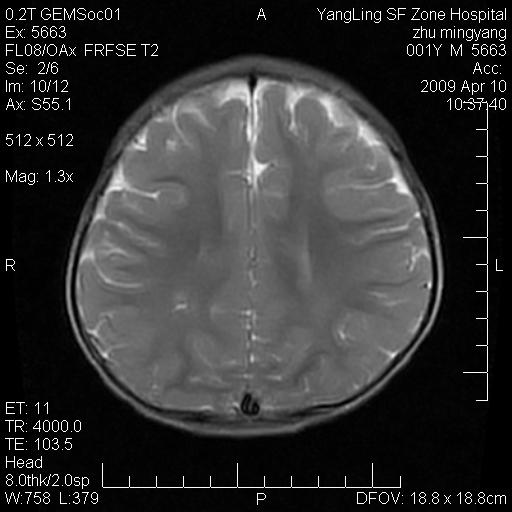

患者:1岁半,两天前外伤收住我院,ct检查小脑占位

考虑星形细胞瘤,建议增强

髓母细胞瘤或血管母细胞瘤,增强后可以鉴别;影像资料见 <。鱼博浪老师的《中枢神经系统ct与mr鉴别诊断》 小脑部肿瘤章节。

髓母细胞瘤或血管母细胞瘤!支持!

支持考虑髓母细胞瘤

考虑----髓母细胞瘤可能性大

考虑髓母细胞瘤或室管膜瘤。

支持髓母细胞瘤。

考虑髓母细胞瘤。

考虑髓母细胞瘤或星形细胞瘤

考虑髓母细胞瘤.

考虑髓母细胞瘤可能性大。

小脑肿瘤.考虑髓母细胞瘤可能.

就病灶部位及临床资料首先考虑髓母.